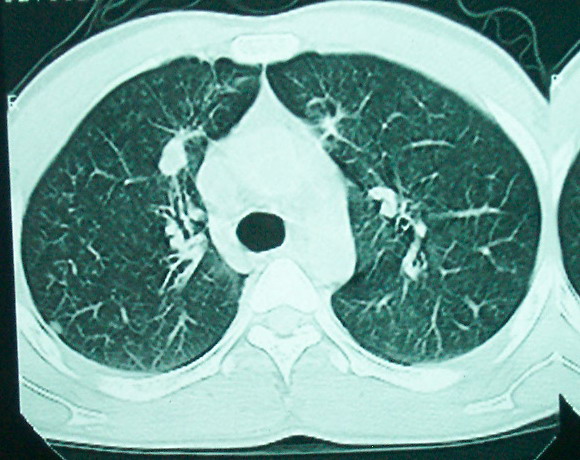

m      37y      发热   咳脓痰月余      ct肺脓肿但住院抗炎治疗后双肺内结节不知该如何解释

治疗后见左肺下野病灶较前缩小但双肺内结节影似无变化请较各位老师该如何下结论    治疗前wbc14.5 治疗后wbc 11.0

结合临床发热,咳痰考虑为血源性肺脓肿,不过双肺结节又在肺的边缘,还是小心一点,抗炎后复查吧

除了肺内多发结节和左肺下叶的浓疡病灶,还应注意满肺散在的小结节影,还有右上肺前段支气管内膜不光整这些细节,结合病史,肺内多发结节应考虑结核性肉芽!

如果你仔细的同层面对比,你会发现所有的病灶均有比较明显的吸收、缩小。病变的形态,特别是脓肿的形态、壁的厚薄、内壁均有很大的变化,均在往好的方面发展。与临床症状、血像均符合,治疗效果比较显著,就是肺脓肿并双肺的化脓性炎症灶。